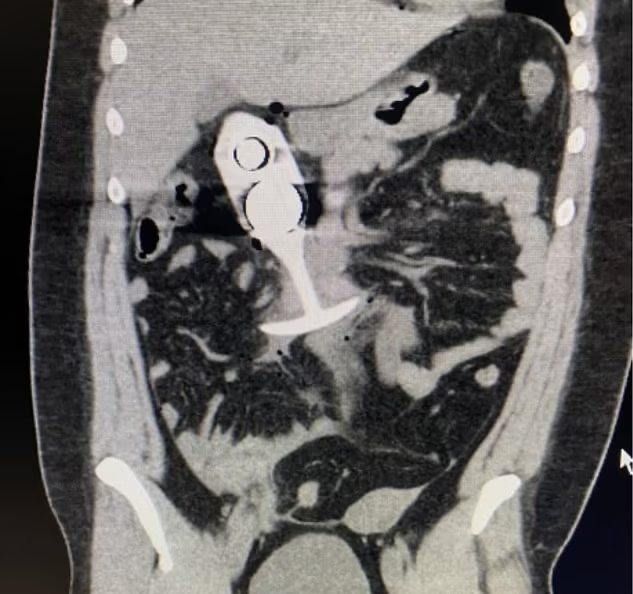

Великобританка едва не умерла во время МРТ из-за анальной пробки. Девушка так заигралась, что просто забыла про игрушку. Раскрыта тайна легендарного скрина, который почти два года форсился в интернетах.

О случившемся стало известно еще в апреле 2023 года. Теперь же СМИ выяснили историю фотки и нашли героиню историю. Оказалось, аксекссуар пролетел со скоростью звука до середины живота (на фото). Поэтому потребовалась срочная операция. Потом дама рассказала, что забыла про девайс, так как считала его безопасным, ибо сделан он из силикона. И не знала, что внутри пробки есть металлическое "ядро". На него и среагировал аппарат.